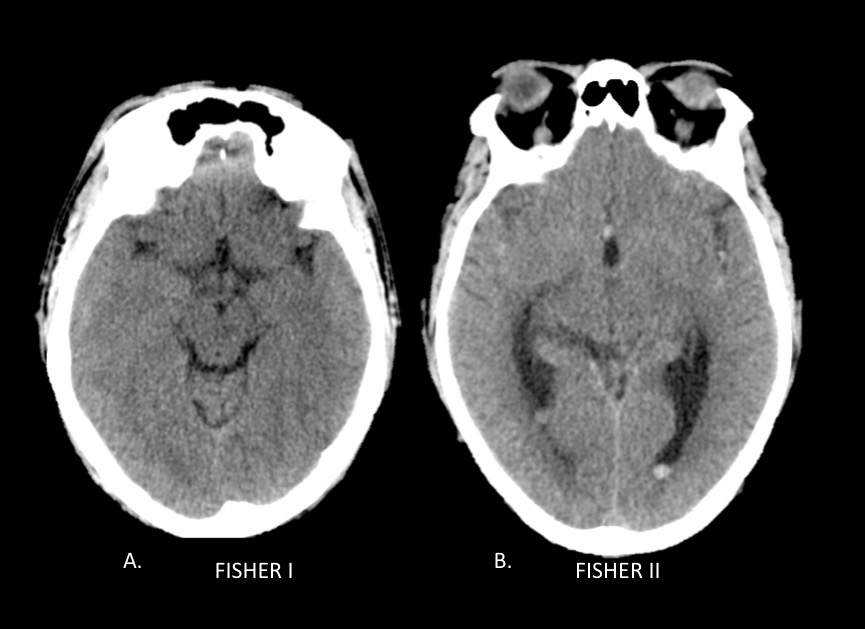

La escala de Fisher es un índice de riesgo de vasoespasmo basado en un patrón de hemorragia definido por tomografía sin contraste (TC) (ver Tabla 5), y la escala de Fisher modificada (también conocida como escala de Classen) es un índice similar de riesgo de isquemia cerebral tardía por vasoespasmo (ver Tabla 6).

| Tabla 5. Escala de Fisher en tomografía para la valoración del riesgo de vasoespasmo en la HSA | |

| Grado | Patrón de HSA en TC de cerebro sin contraste |

| 1 | No HSA o hemorragia intraventricular (HIV) |

| 1 | HSA difusa o capa fina en todas las capas verticales (en cisura interhemisférica, cisterna insular, cisterna ambients) de menos de 1 mm de espesor |

| 2 | Hematoma localizado y / o capas verticales de 1 mm o más de espesor |

| 3 | Hematoma intracerebral o intraventricular con sangre subaracnoidea difusa o sin sangre |

Fig. 1a. Escala de Fisher modificado en TC de cerebro sin contraste, cortes axiales. A. Fisher I y B. Fisher II.

Fig. 1b. Escala de Fisher modificado en TC de cerebro sin contraste, cortes axiales. C. Fisher III y D. Fisher IV.